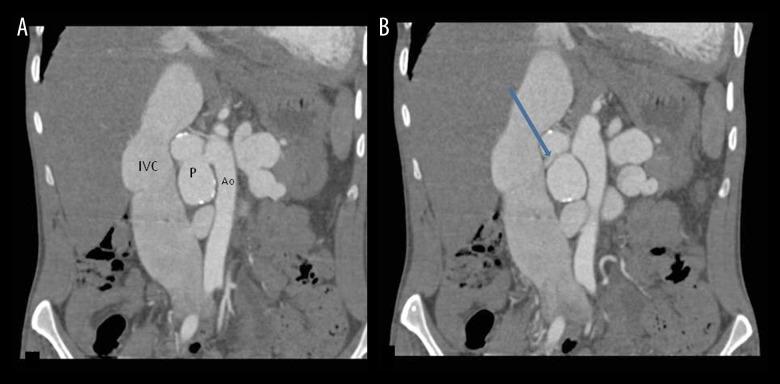

A 29-year-old male presented to the cardiology department with complaints of breathlessness, abdominal pain and hematuria for the last 6 months. On clinical examination there was evidence of audible bruit over the abdomen. He had a past history of a gunshot injury around two years back. CT angiography revealed a large partially calcified pseudoaneurysm arising from the right lateral wall of the abdominal aorta with the neck of the pseudoaneurysm at juxtarenal location with a fistula between the anterior wall of the pseudoaneurysm and the posterior wall of the right renal vein. There was an associated incidental finding of circumaortic left renal vein with gross aneurysmal dilatation of both pre- and retro-aortic part of the renal vein.

Delayed presentation of aortic pseudoaneurysm with its fistulous communication with the right renal vein is a rare entity. CT angiography is a non-invasive modality for diagnosis of the exact site of communication, length of aneurysm, proximal and distal extent of the affected segment and its relationship with surrounding structures.